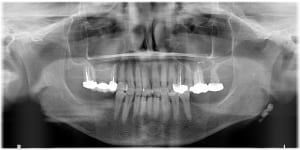

20-04-2021 Panoramique Début.JPG

10-07-2025 Panoramique Fin.JPG